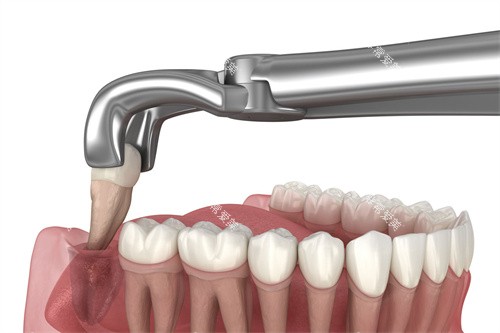

横向阻生智齿拔除是一项精细的外科手术,通常包括以下步骤:

局部麻醉确保手术区域完全不痛;

牙龈切开和翻瓣,暴露下方骨组织;

必要时去除部分覆盖骨质;

根据情况将智齿分割成若干部分逐一取出;

然后清理创口并缝合。

手术时间因难度而异,简单病例可能20分钟内完成,复杂情况则需1小时以上。

术中患者会感受到压力而非疼痛,配合医生指令保持头部稳定非常重要。